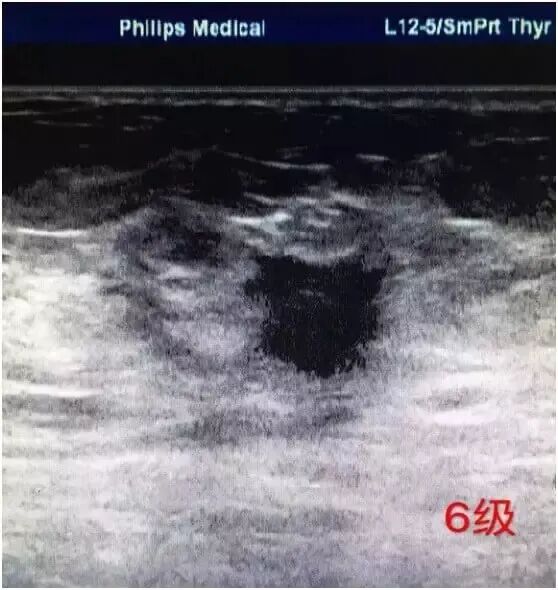

6级

是新增加的分级类型,这一分级用在病理活检已证实为恶性但还未进行治疗的影像评价上。主要是评价先前活检后的影像改变,或监测术前新辅助化疗效果的影像改变。